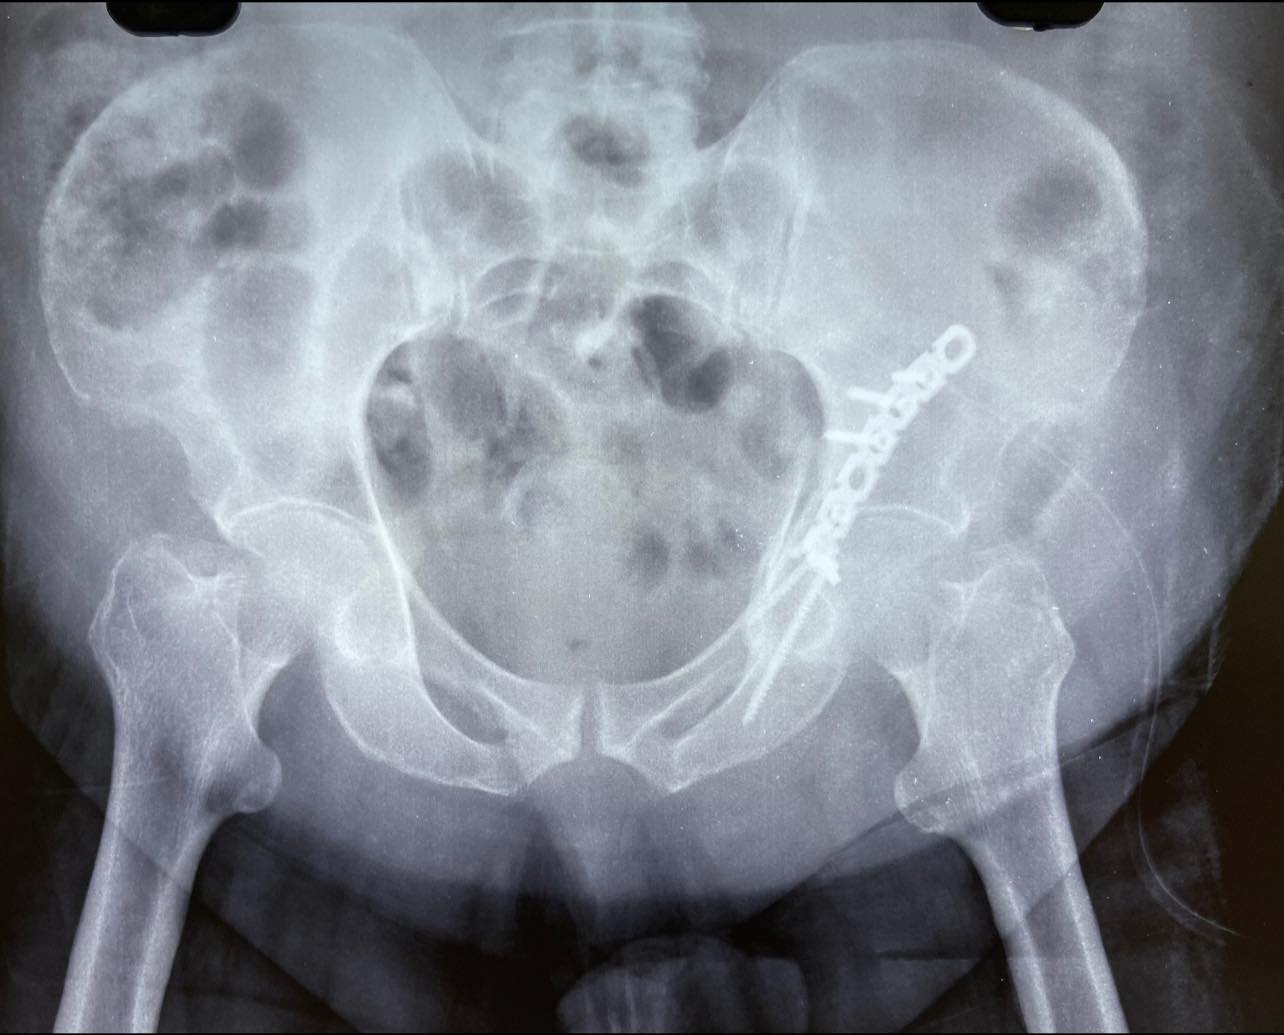

Considering the general condition and weight of the patient just fixing the posterior column felt like the right thing to do, the joint congruity is within the range of standard deviation.